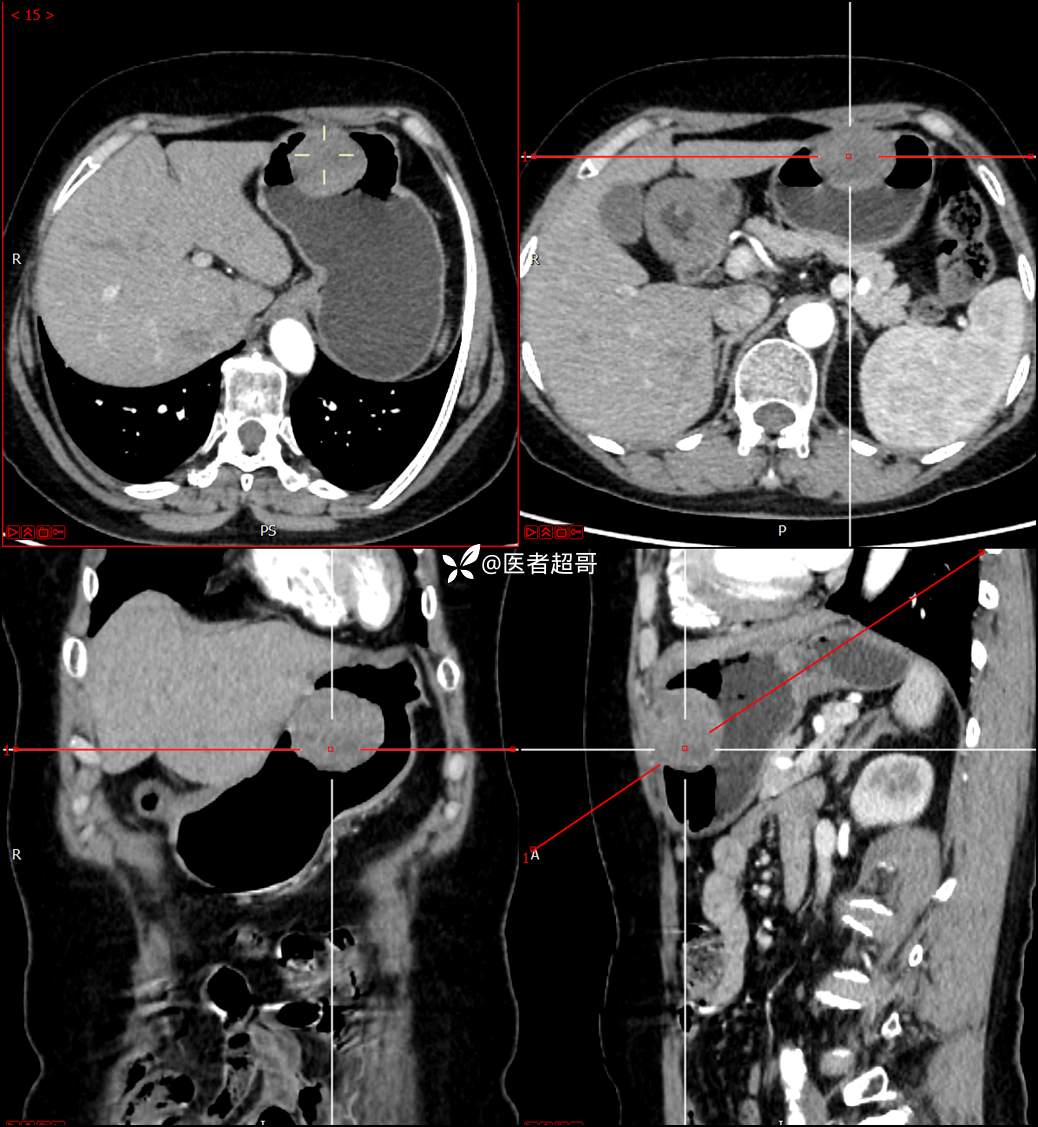

【影诊笔记759】胃体巨大隆起,间质瘤?神经鞘瘤?平滑肌瘤?请鉴别诊断!有结果!

患者半月前无明显原因及诱因出现上腹部疼痛不适,以夜间腹痛为主,无放射性疼痛,间断嗳气,无反酸烧心,无腹泻黑便,于我院门诊行胃镜显示:胃体前壁巨大隆起型病变。